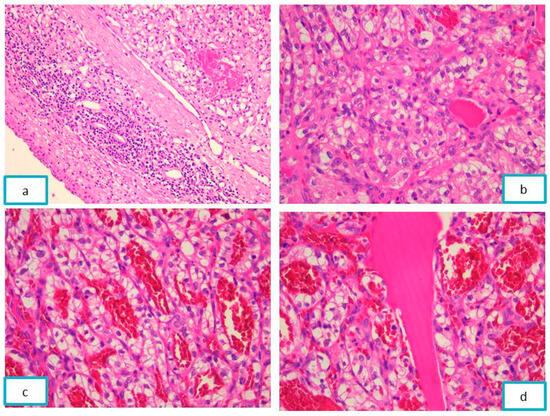

2.1.2. Pathological Findings

2.2.2. Pathological Findings

2.3.2. Pathological Findings